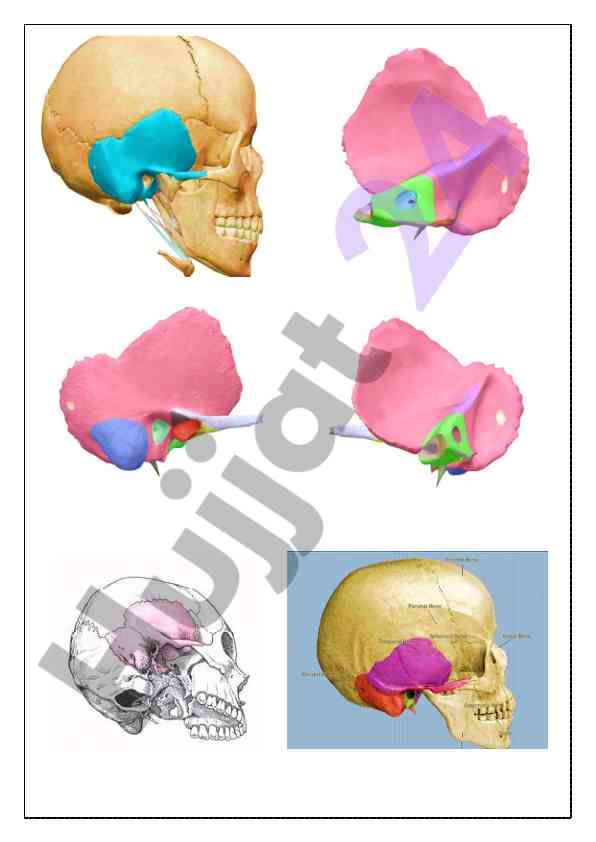

Kalla skeleti va chakka suyagi haqida umumiy ma'lumotlar taqdim etilgan o‘quv qo‘llanma. Anatomiyaga oid asosiy tushunchalar va strukturalar izohlangan.